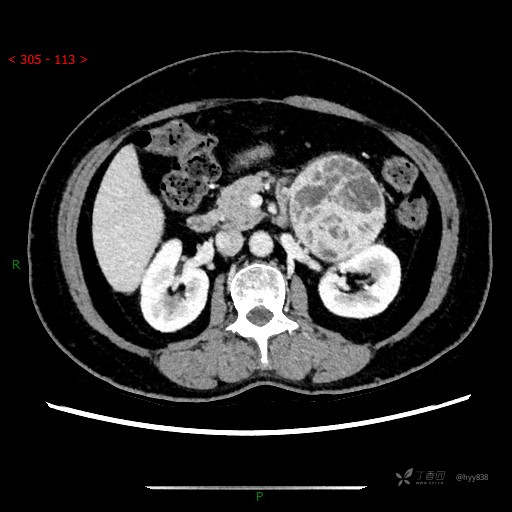

讨论:病变性质?